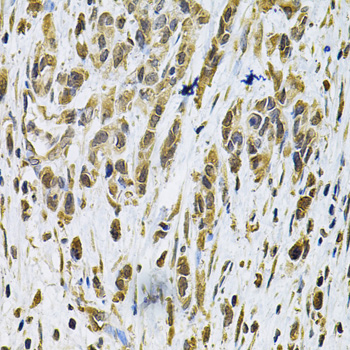

Facts about Transforming protein RhoA.

Plays an important role in cleavage furrow formation. Stimulates PKN2 kinase activity.

| Gene Name: | RHOA |

| Uniprot: | P61586 |

Cell membrane; Lipid-anchor; Cytoplasmic side. Cytoplasm, cytoskeleton. Cleavage furrow. Cytoplasm, cell cortex. Midbody. Cell projection, lamellipodium. Cell projection, dendrite. Localized to cell-cell contacts in calcium-treated keratinocytes (By similarity). Translocates to the equatorial region before furrow formation in a ECT2-dependent manner. Localizes to the equatorial cell cortex (at the site of the presumptive furrow) in early anaphase in an activated form and in a myosin- and actin-independent manner.